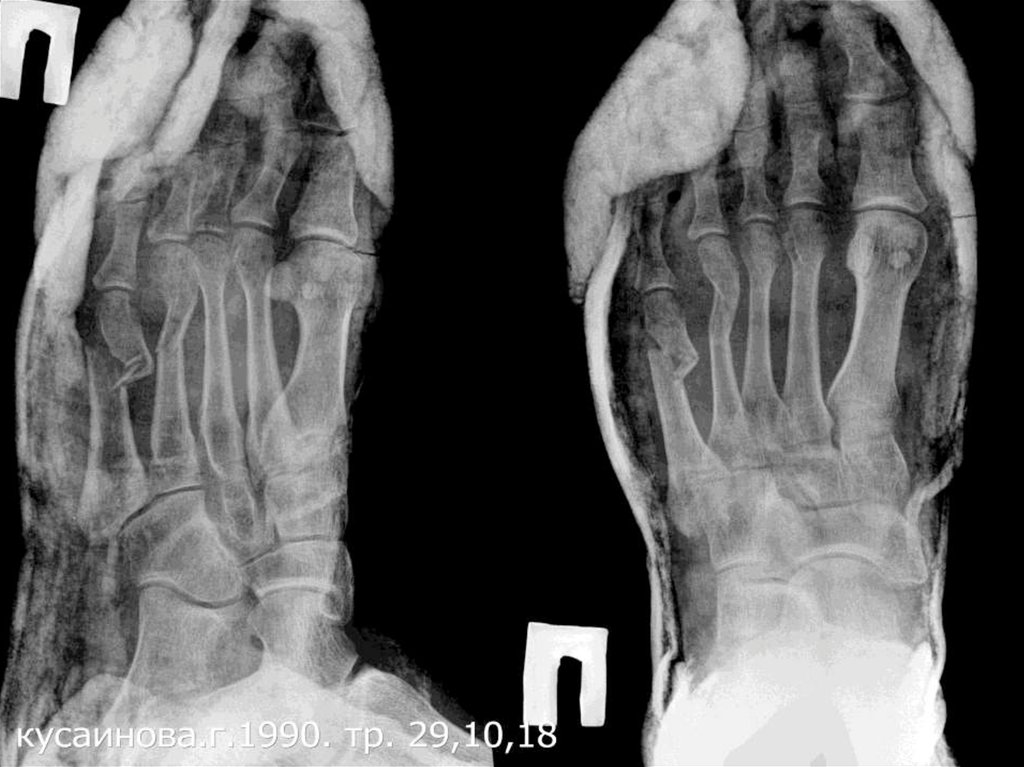

2. 1.КУСАИНОВА ГУЛЬФИЯ    31.01.1990 (28жас)

1.КУСАИНОВА ГУЛЬФИЯ 31.01.1990

(28жас)

Диагноз: IV, V оң табан сүйектерінің жабық

сынуы, ығысумен.

Операция: V табан сүйегінің ашық репозциясы,

остеосинтез пластинамен. IV табан сүйегінің

жабық репозицясы, остеосинтез спицамен.